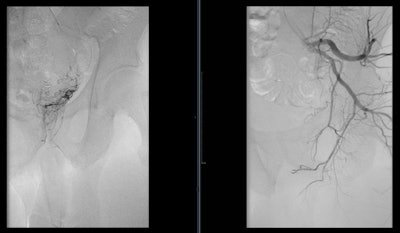

Technically, PAE is challenging. Unnecessary catheterization increases procedure time and radiation exposure. Knowledge of anatomical features to identify and catheterize target arterial branches is paramount to achieve the best clinical outcomes. The prostate receives its arterial supply via the medial and the capsular/lateral branches but is variable among patients.

Assis et al proposed an angiographic classification of prostate artery anatomy and analyzed 286 pelvic sites to find that most inferior vesical arteries and their prostatic branches arise from the internal pudendal artery. Conebeam CT (CBCT) angiography has been utilized to evaluate the many variants of the prostatic artery. With direct contrast injection and 3D angiography, subtle prostatic feeders are better identified when compared with digital subtraction angiography and CT angiography.

Traditionally, PAE has been performed via a transfemoral approach (TFA), but the transradial approach (TRA) has garnered increased interest recently. Evidence has suggested that TRA results in shorter postprocedure hospital stays, decreased access-site complications, and improved patient satisfaction. This method would also allow patients to ambulate immediately post-PAE, which could facilitate urination. The distance from the forearm to pelvis along with the arterial tortuosity and previously mentioned variant anatomy has deterred initial attempts for PAE via TRA. Further, prior to selecting TRA patients, collateral circulation must be adequate as determined using a Barbeau test (i.e., a modified Allen test with a pulse-oximetry device).